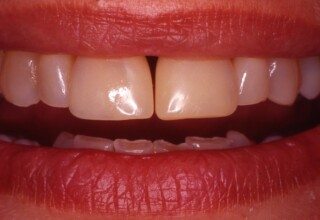

Όψεις Σύνθετης Ρητίνης

Οι όψεις ρητίνης προσφέρουν έναν οικονομικό τρόπο αισθητικής βελτίωσης της εμφάνισης των προσθίων δοντιών ενίοτε και των προγομφίων. Οι δυνατότητες τους πολλές, μπορούν να κάνουν και θαύματα! Ο μονός περιορισμός η κλινική ευχέρεια και η φαντασία του επεμβαίνοντος. Σε αυτήν την ασθενή οι τέσσερεις άνω τομείς είχαν ο καθένας το δικό του πρόβλημα(δυσχρωμία, απόκλιση) και επιπλέον: διαστήματα, πολλαπλές αποχρώσεις, κακή σχέση μεταξύ τους και με τα ούλα. Αποκαταστάθηκαν με τέσσερεις άμεσες όψεις ρητίνης (η μια πάνω σε στεφάνη πορσελάνης εμφυτεύματος!!!) οι οποίες κατασκευάστηκαν ενδοστοματικά!